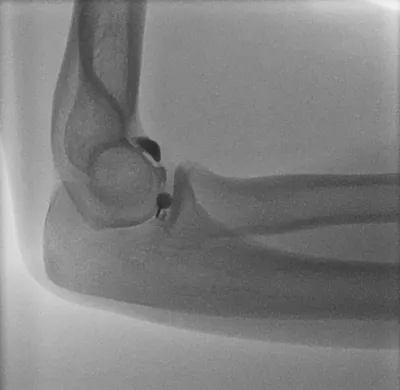

Sail sign of elbow effusions

Elbow

4/10/2026